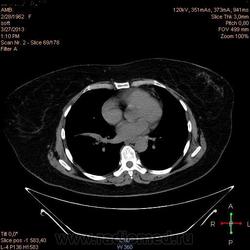

Здравствуйте, коллеги .Нужна помощь.Больная страдает Бронх.астмой.Беспокоять кашель,одышка , слабость, боль левой грудной клетке.Была температура 37,5- 38,0.Данный момент получает цефомизин темпер нормализовалось.Хочеть стационарное леч.Обратите пожалуиста на молочные железы, справа была операция год назад .Беспокоять боль правой мол.железе.

Во-первых, нет дайкомов. По представленным изображениям, изменения в левом легком дифференцировал бы между ТЭЛА мелких ветвей и организующей пневмонией, справа - пока вариантов нет (нужны дайкомы).

+1. Диф. диагностика между ОП и ТЭЛА обоих легких. Исключить ТЭЛА методом КТ с в/в боюсным контрастированием.